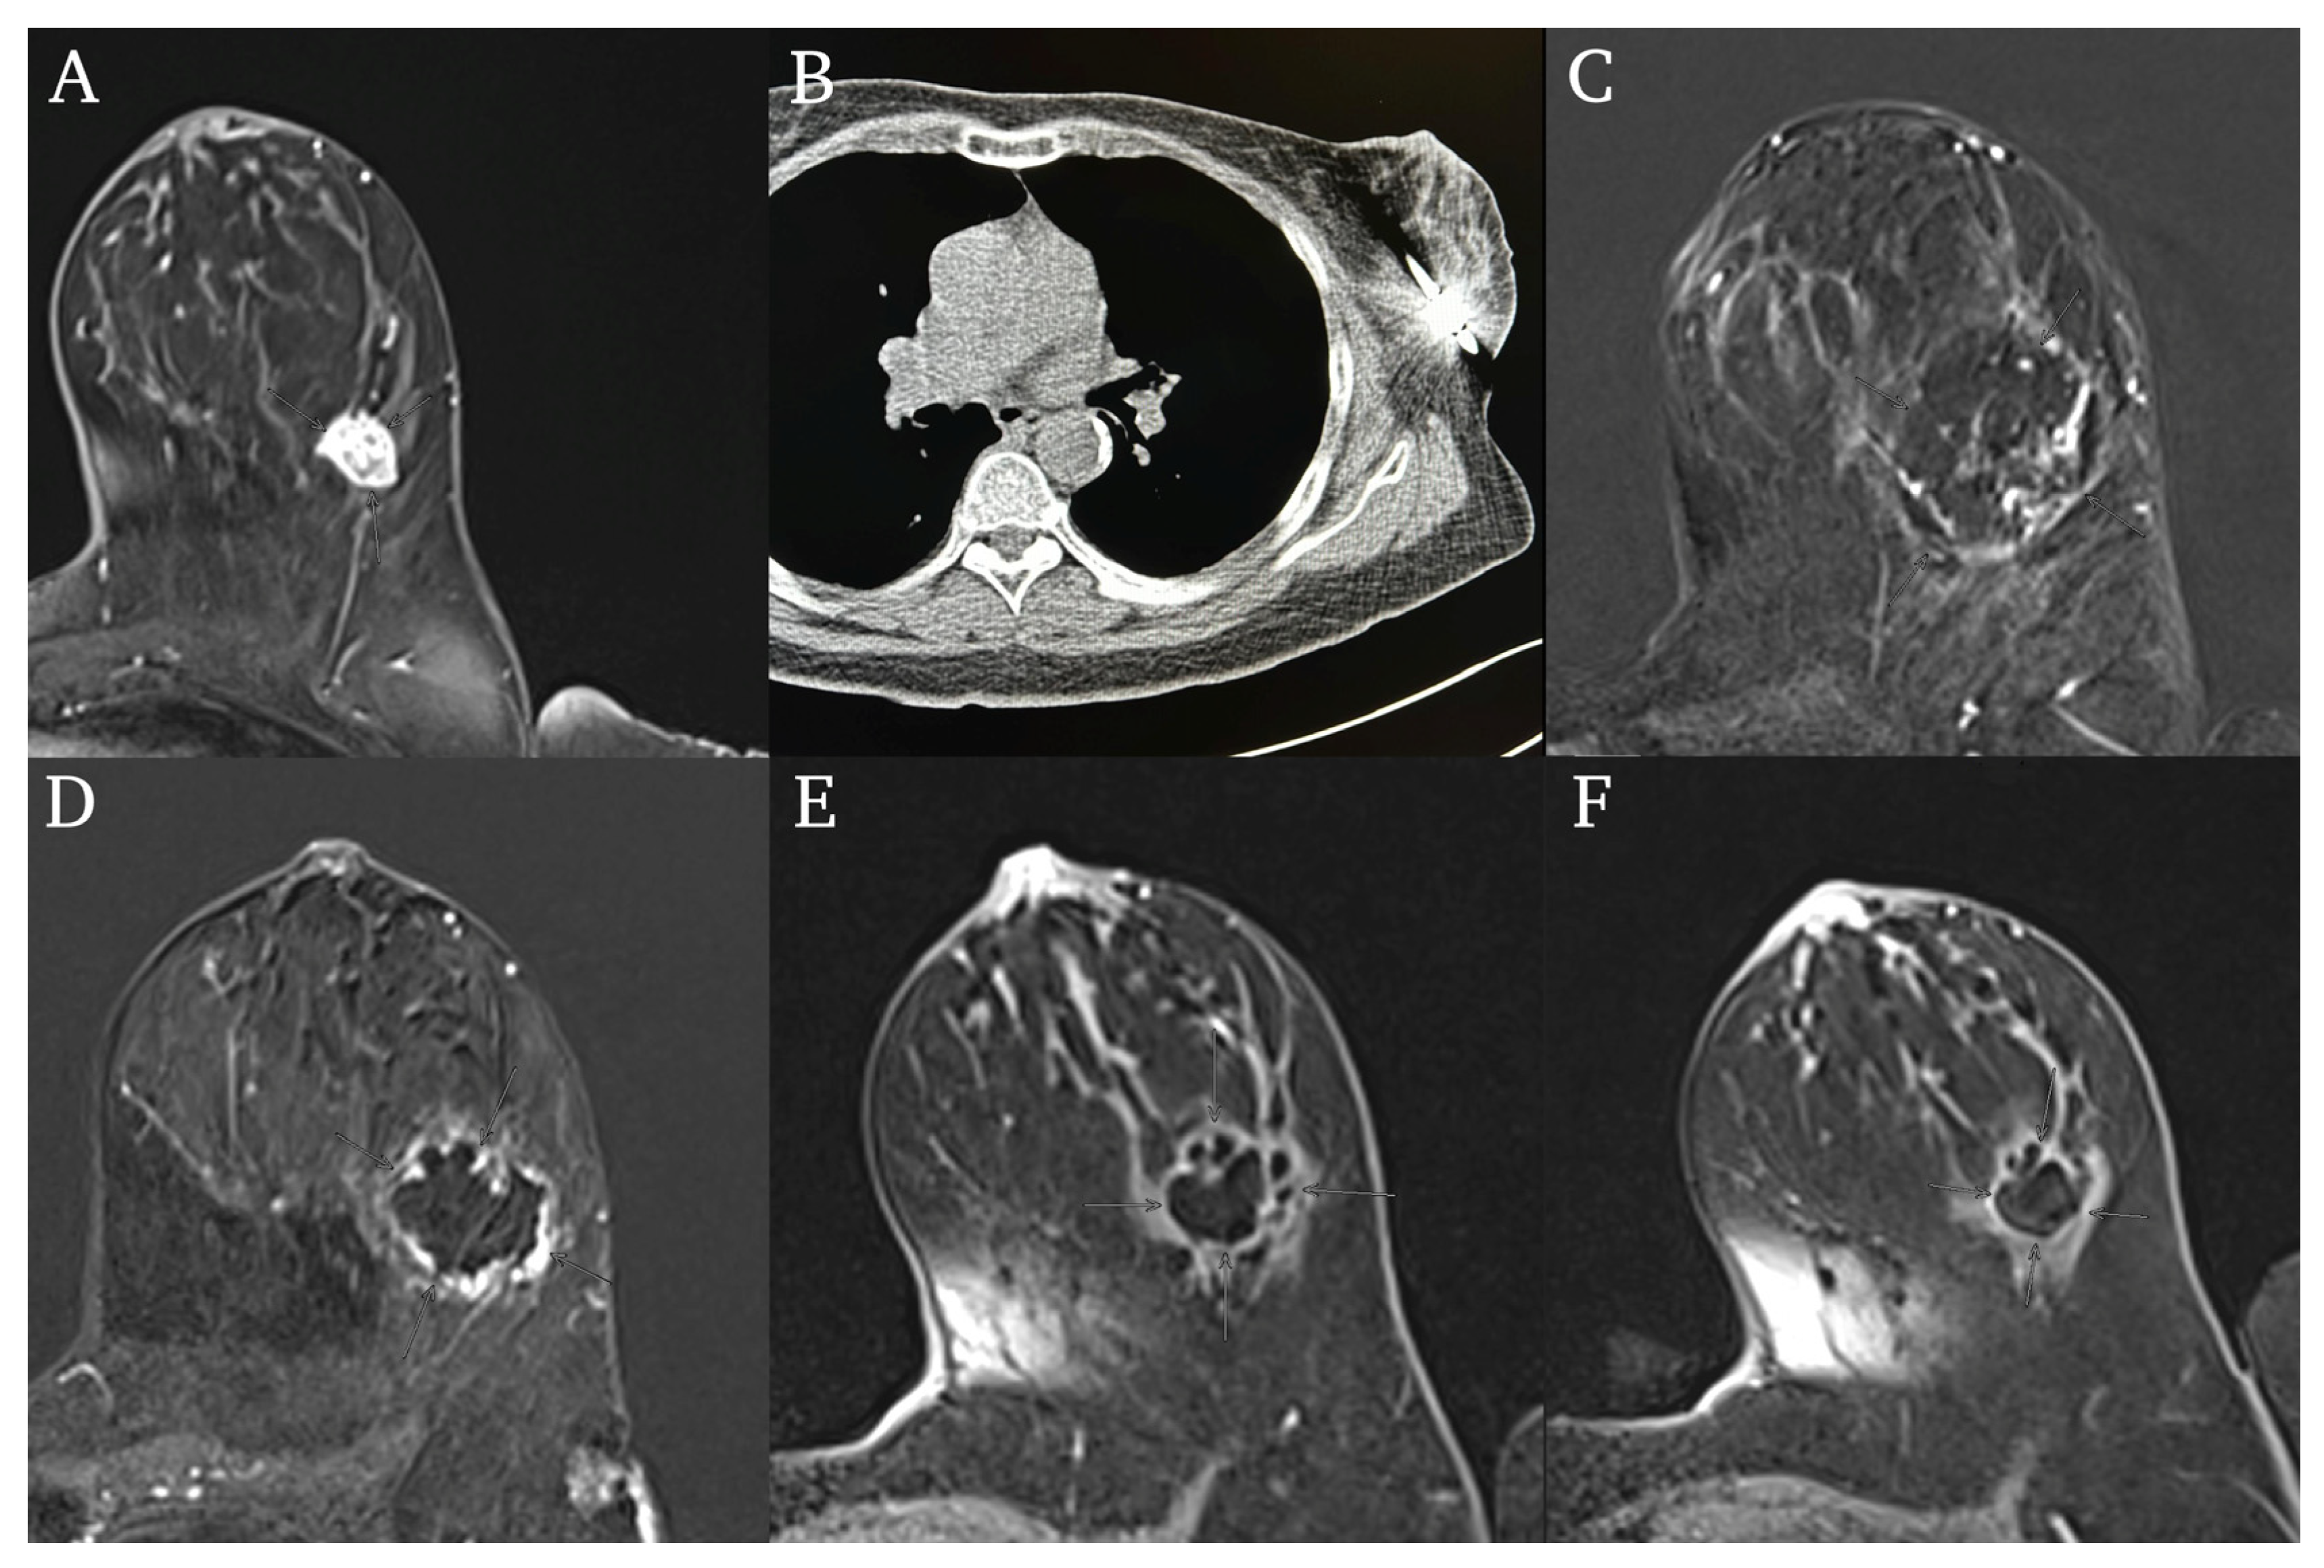

2.3. Cryoablation Procedure

3.3. Ablation Procedure

3.4. Outcome and Survival